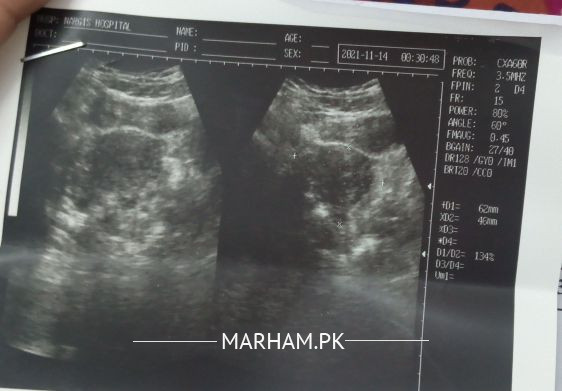

A Friend of mine got tested as she's having problem in conceiving and it's been more than a year of her marriage she got diagnosed about PCOs the level of prolactin is 22 CBC is normochromic normocytic

Serum fsh , LH and TSH level on 2nd day of periods

serum FSH ,LH,TSH